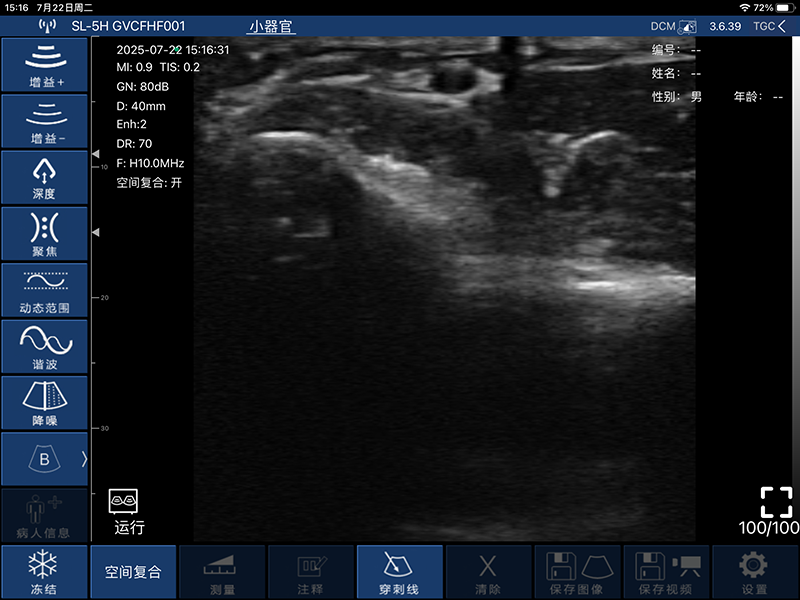

带指套探头的掌上彩超,小小的掌超主机放在口袋可随处走,手指套着探头即可完成打图成像,让手不再需要握着探头而可解放出来还能拿其他东西,特别适合术中等应用

- 探头频率:7.5/10MHz

- 扫描宽度:25mm

- 扫描深度:10/20/30/40mm,可调

- 显示模式:B、B/M、COLOR、PDI、PW

- 穿刺辅助功能:平面内穿刺引导线功能,平面外穿刺引导与血管自动测量功能